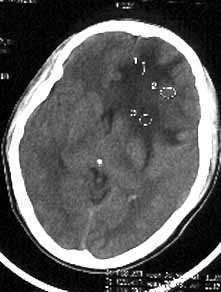

男性,36岁,头痛数年,近期伴有视蒙。

ct诊断:左额颞部脑膜瘤。